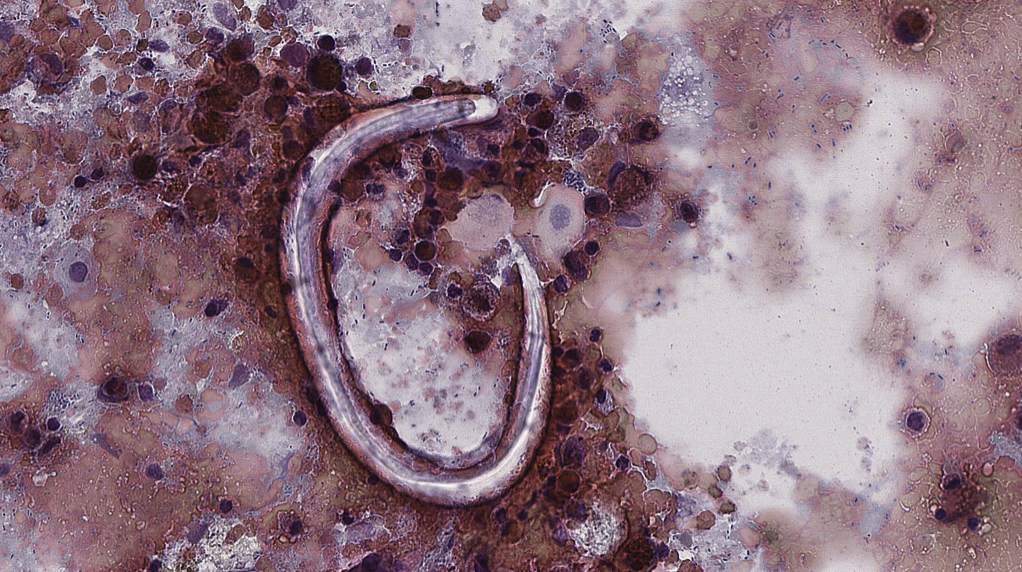

Foto 2: Larva ondulada con un extremo fino y otro achatado. Pap 40X

Foto 3. Larva que muestra que un extremo es delgada probablemente el posterior (flecha) Pap 40X